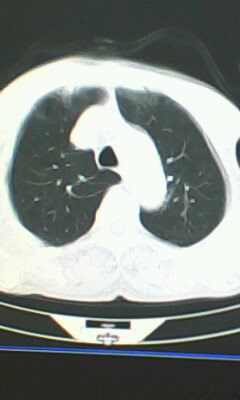

胸廓呈桶状,双膈低平,肺实质及纵隔未见明显异常密度灶考虑肺气肿.

肺气肿

以下是引用ctkz987在2010-5-5 21:30:00的发言:[br]胸廓呈桶状,双膈低平,肺实质及纵隔未见明显异常密度灶考虑肺气肿.

弥漫性肺气肿 但内胆管轻度扩张

临床诊断:copd

慢阻肺是临床诊断,未见明显异常。